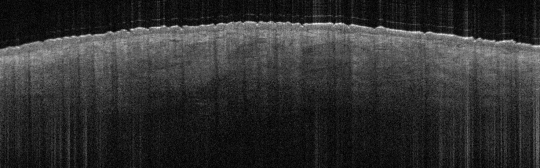

VA1: Left Forearm, Actinic Keratosis